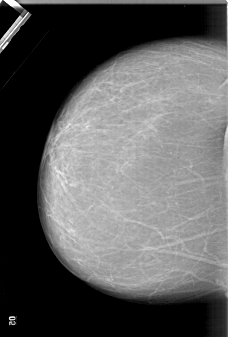

A_1333_1.LEFT_MLO

LEFT_MLO LINES 6541 PIXELS_PER_LINE 4306 BITS_PER_PIXEL 12 RESOLUTION 43.5 NON_OVERLAY